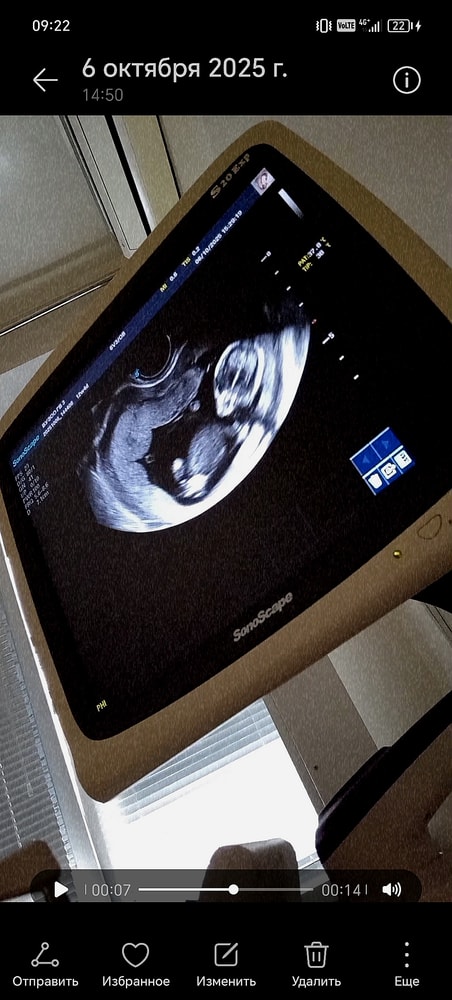

УЗИ, КТГ, доплерДевочки привет , у меня был первый скрининг месяц назад, хотелось бы узнать кто будет у меня , хотя как-то глупо звучит, всего то 12 неделя была, но все же , очень интересно, а сейчас идёт 18 неделя , пока что не чувствую шевеления , может не обращаю внимания

Как будто бы там мальчуган😁